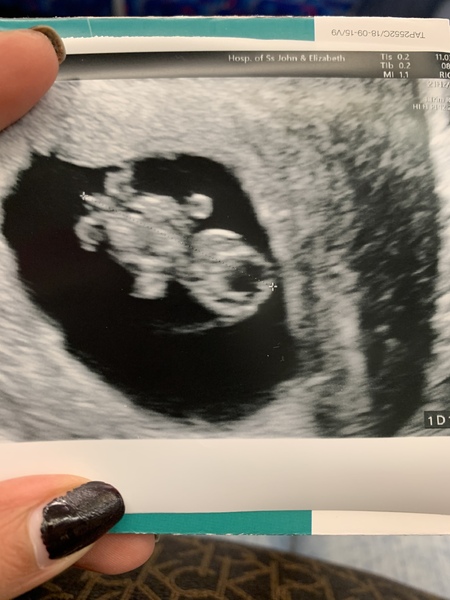

Good morning ladies! Happy to report good news! My baby has grown in size (it is 19mm now) and caught up so I’m actually 8+4 today. We saw the arms, legs and the heartbeat. Absolutely amazing! I am so so so grateful for this beautiful miracle! My doctor suggested to do the harmony test to check Down syndrome etc. We’ll get the gender tested at the same time, too as I’m too impatient to wait. Apparently that’s a private one and is more accurate than the NHS one. I’m booked in for that on 30th March which will also be my next scan. Good luck to all the other ladies with scans today! Keeping my fingers crossed for more positive news XX

@Firevie Wonderful news!! I'm so glad!! Gorgeous little baby growing away there.

@Firevie Great news! And lovely scan photo too ❤️